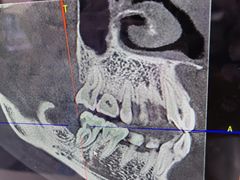

• Dr.Z dental仁康种植矫正中心

• -Dr.Z dental仁康种植矫正中心